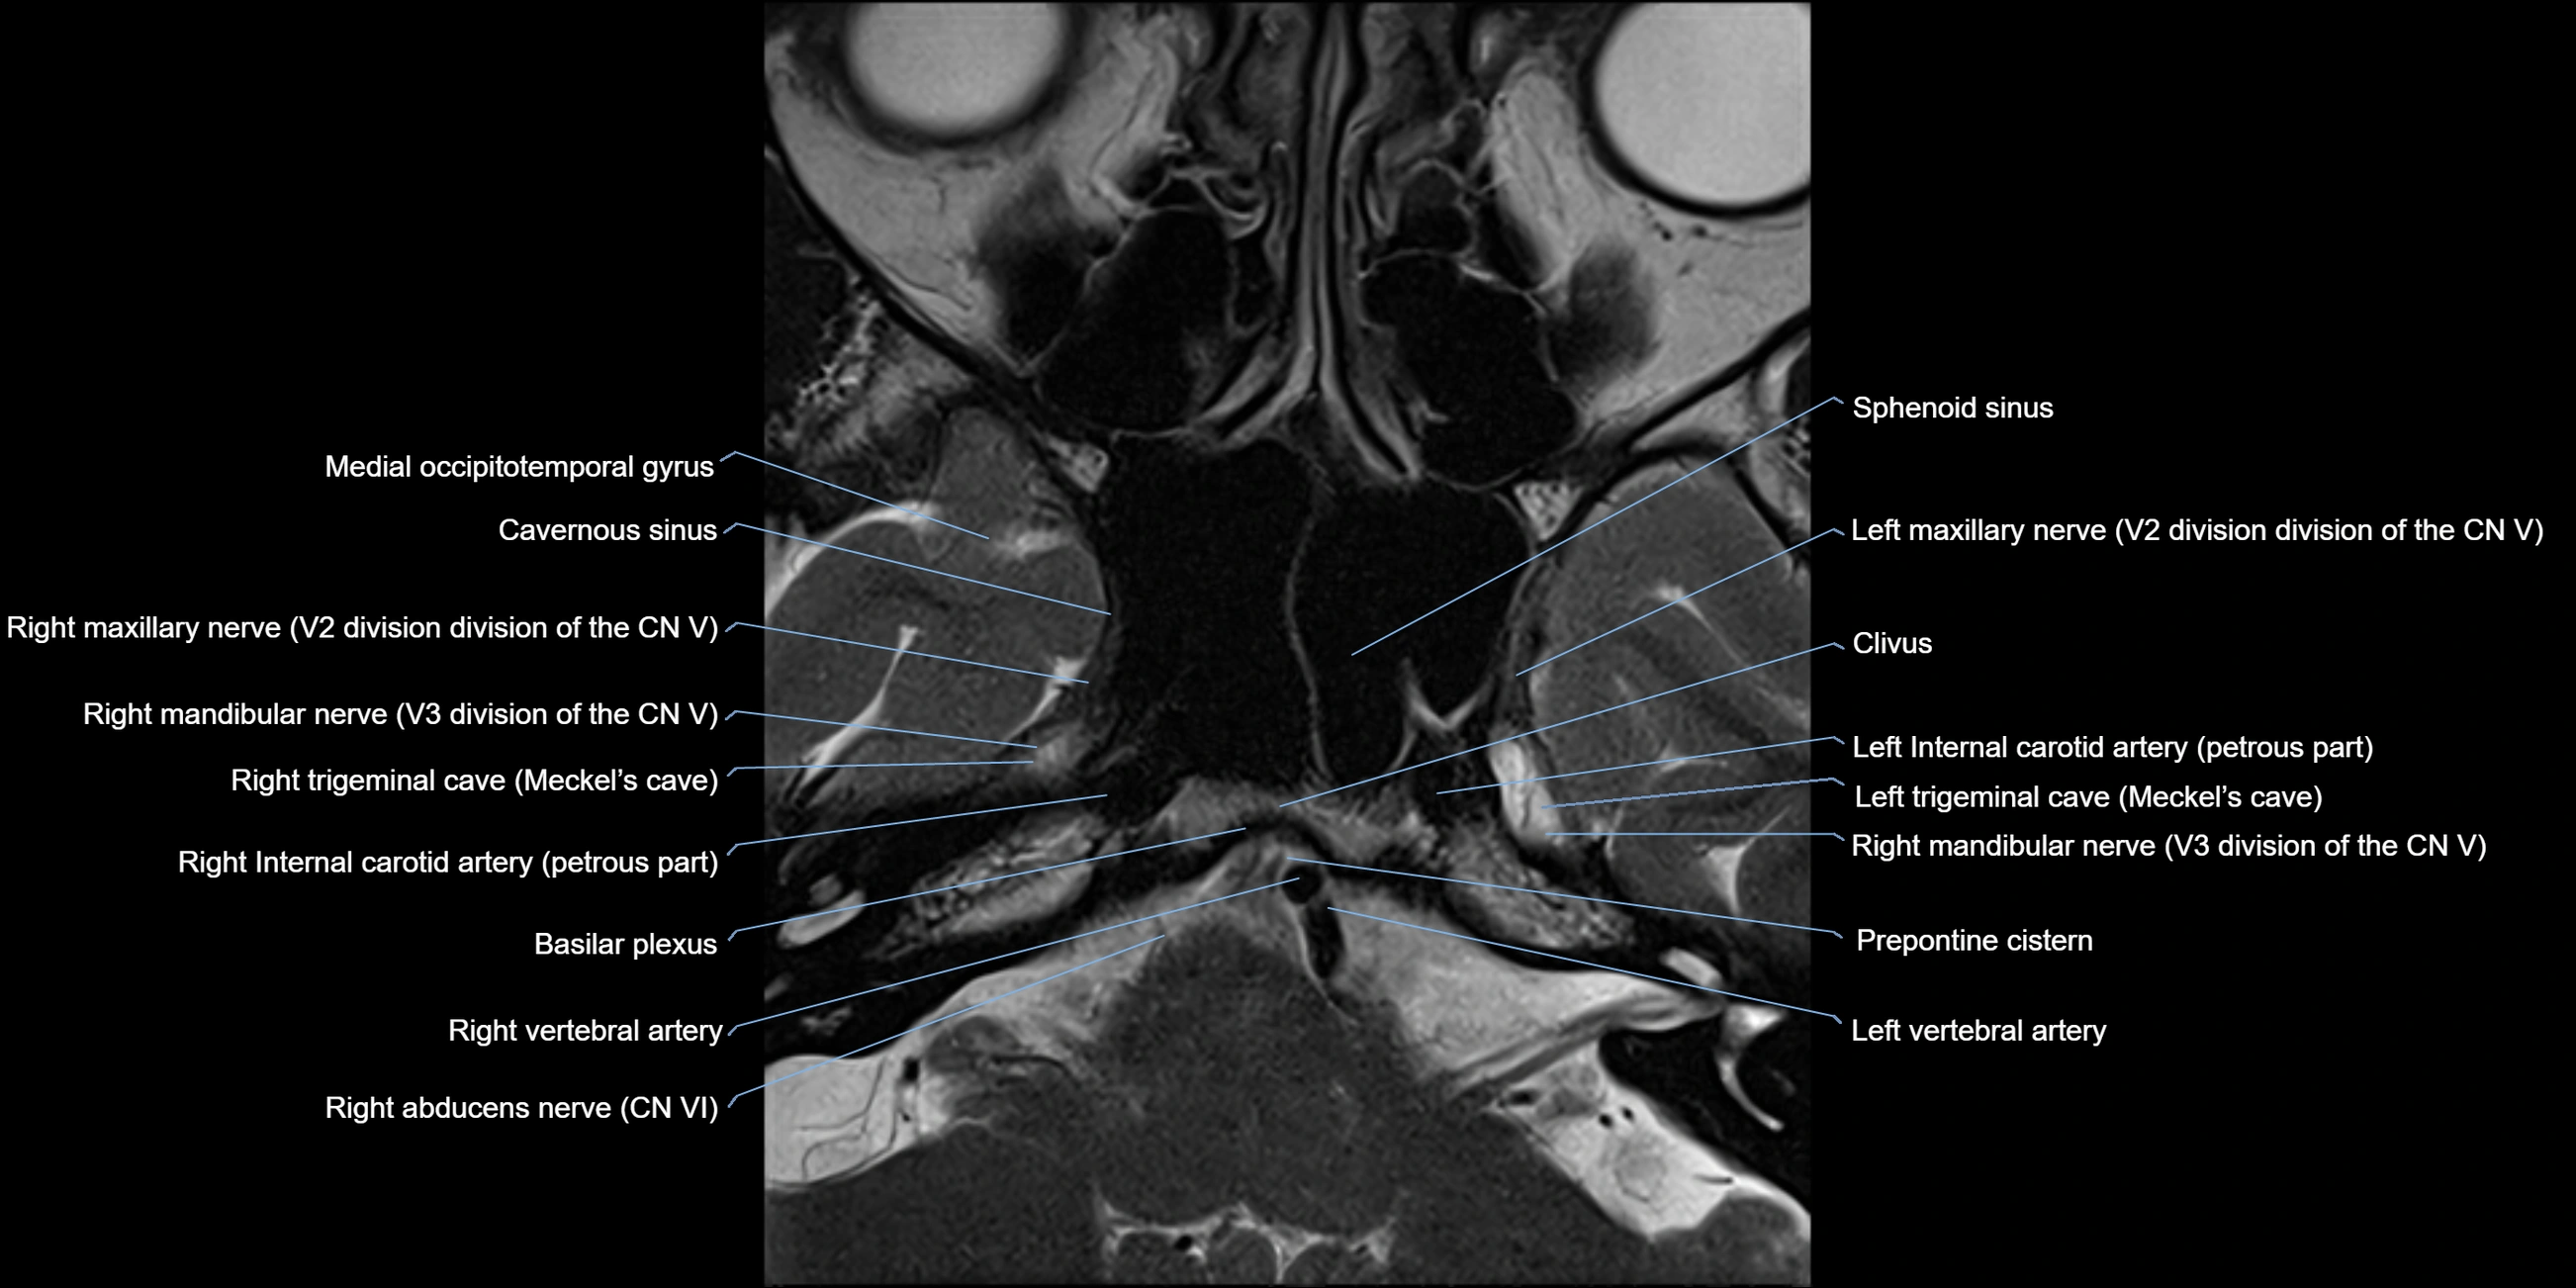

MRI Appearance

-

The abducens nerve is a small, thin, linear structure

Best visualized on high-resolution T2-weighted 3D MRI sequences (e.g., FIESTA or CISS)

Seen as a hypointense (dark) line running from the brainstem at the pontomedullary junction, traversing the prepontine cistern, and entering Dorello’s canal under the petrosphenoidal ligament, then into the cavernous sinus, and finally the orbit

May be challenging to visualize in standard MRI due to its small size

Pathology may be inferred by absence, displacement, or enhancement of the nerve

MRI images